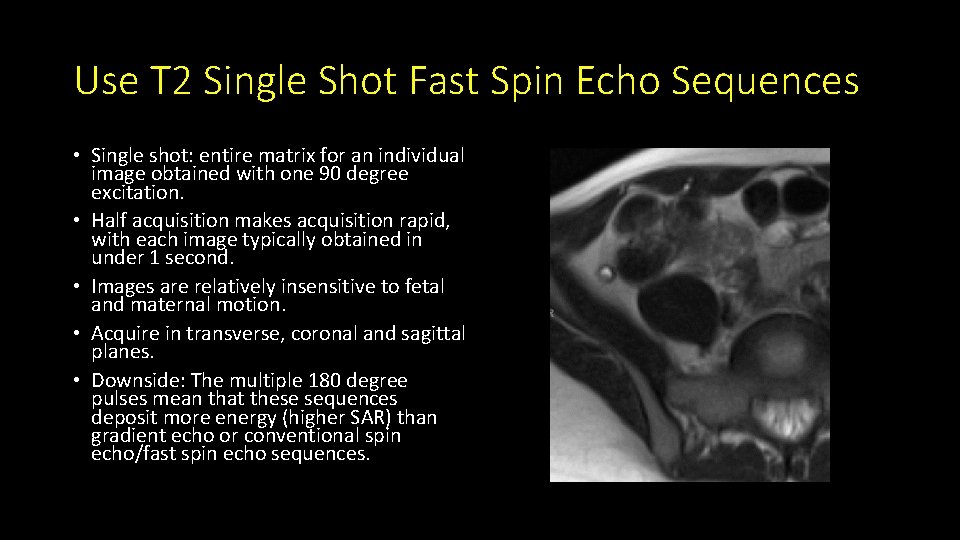

Use T 2 Single Shot Fast Spin Echo Sequences • Single shot: entire matrix for an individual image obtained with one 90 degree excitation. • Half acquisition makes acquisition rapid, with each image typically obtained in under 1 second. • Images are relatively insensitive to fetal and maternal motion. • Acquire in transverse, coronal and sagittal planes. • Downside: The multiple 180 degree pulses mean that these sequences deposit more energy (higher SAR) than gradient echo or conventional spin echo/fast spin echo sequences.